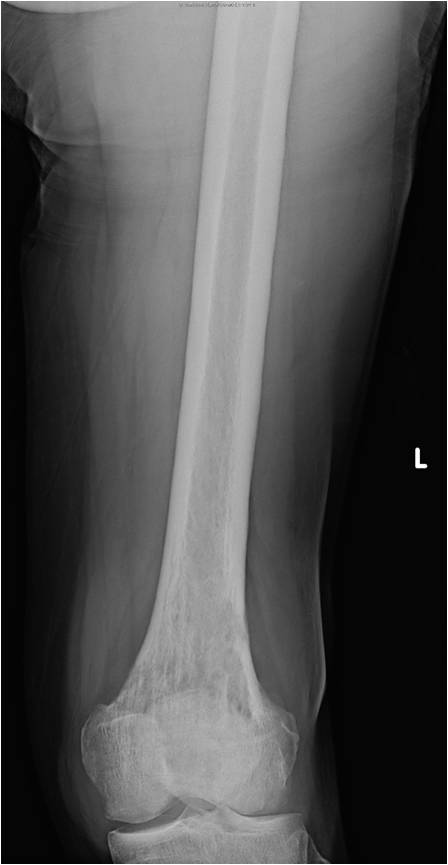

On radiographs, most MFHs of Bone are located in the metaphysis and present as purely osteolytic permeative lesions without a periosteal reaction and without mineralization (Fig. 1 &2). On MR images, MFH of Bone has ill-defined margins usually with cortical destruction of bone and extension into the soft tissues. It is usually hypo- or isointense to muscle on T1-weighted images (Fig. 3) and heterogeneous high intensity on T2-weighted images (Fig. 4-6).

Fig. 1

Fig. 1 & 2: Plain x-rays of an MFH of the distal femur. AP (Fig. 1) and Lateral (Fig. 2) view shows a permeative lytic lesion in the distal femur without a periosteal reaction and without mineralization. The lesion is poorly circumscribed.